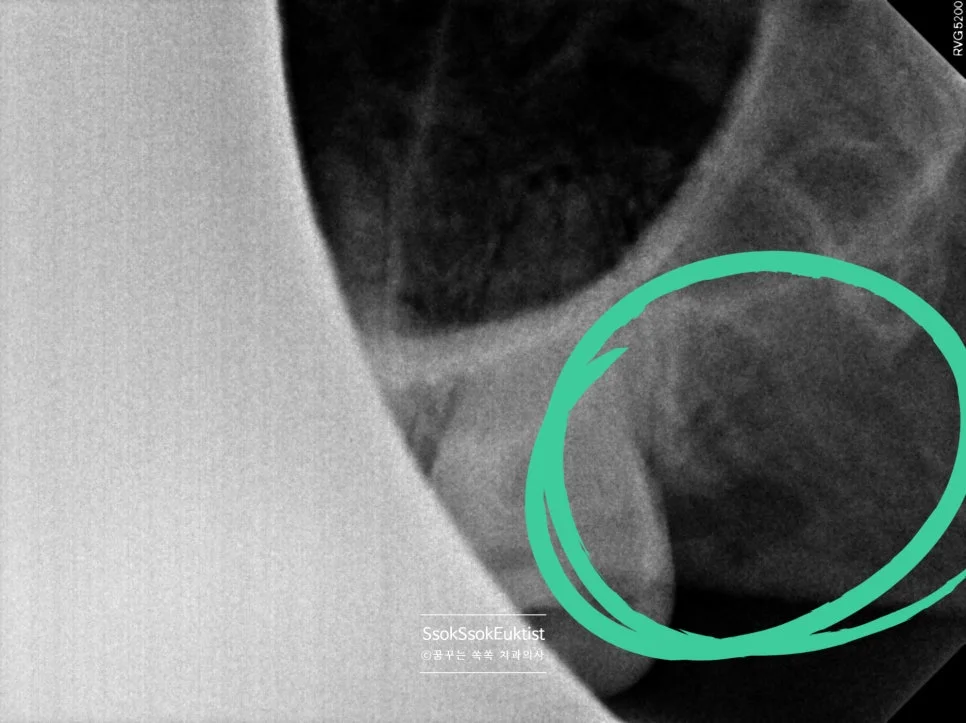

사랑니 발치 후 우측 하악 치근단 X-ray 초록 원 표시

우측 하악 발치 완료 (초록 원)